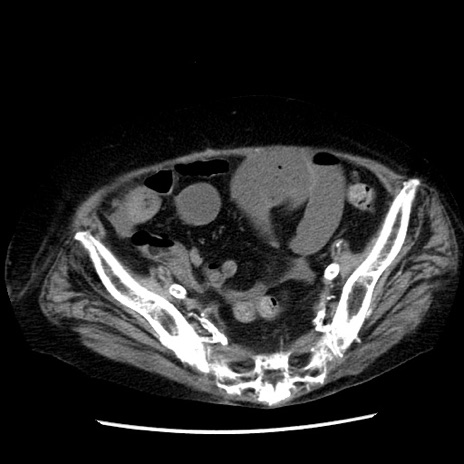

症例14(横断像)

【症例】 90歳代女性

【主訴】 腹痛・嘔吐

【現病歴】今朝から左側腹部痛を認めた。 経過観察していたが、嘔吐を認めたため来院。

【既往歴】 子宮癌術後

【身体所見】 意識清明、BP 127/54mmHg、P 98bpm Sp02 95%(RA)、BT 35.8°C、腹部平坦・軟腸ぜん動音聴取良好、右下腹部圧痛(+) 反跳痛なし

【データ】WBC 9800、CRP 0.46